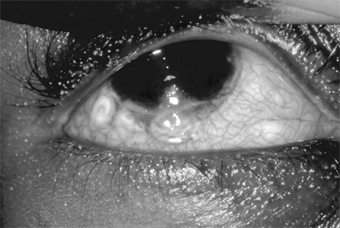

Figure 5-10

Figure 5-10: Acute hypersensitivity with moderate tylosis, moderate to marked chemosis and mild injection of the conjunctiva. Note that the eye seems to be "sinking" into the surrounding tissue.